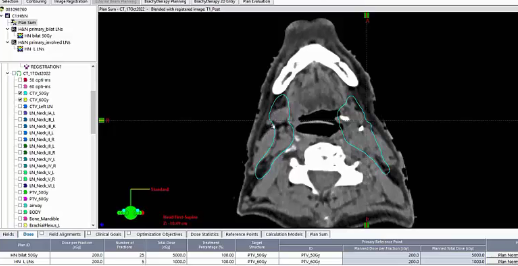

keep esophagus off 2 cm, 4-5 field VMAT, push a lot harder, omit level 6, PTV, 15 Gy, bilateral tongue, node positive, post-op tonsil, 60 Gy margins, negative margins, chemoradiation, ipsilateral neck, cisplatin, T2N2, tonsillectomy, left neck dissection, SCC, CTV, uvula, soft palate